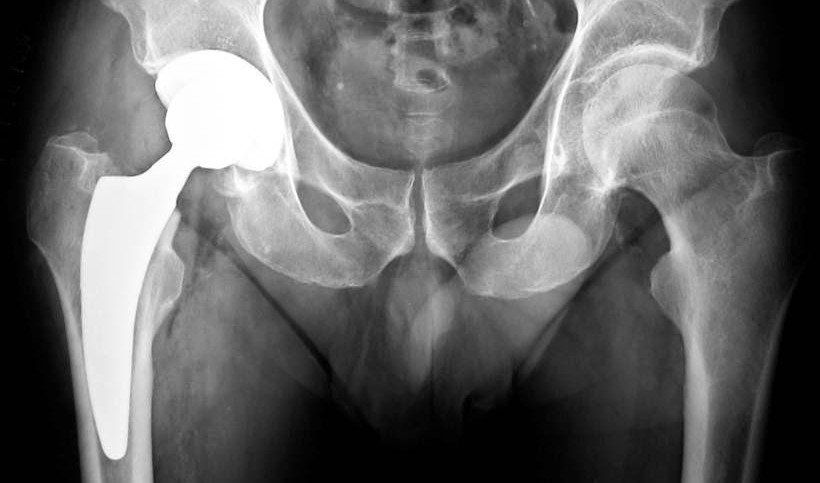

L’intervento di innesto di una protesi anca mini invasiva comporta la sostituzione della testa del femore e dell’acetabolo con componenti in titanio e un inserto in polietilene.

Ma la protesi anca mini invasiva dove si colloca? La protesi totale mininvasiva dell’anca viene inserita per sostituire l’articolazione coxofemorale.

La protesi dell’anca è costituita da una componente femorale, che va inserita nel canale femorale, da una testina femorale e da una componente acetabolare, che viene inserita nel bacino.

Su quest’ultima, si inserisce l’inserto in polietilene, che agevola lo scorrimento delle superfici delle protesi.